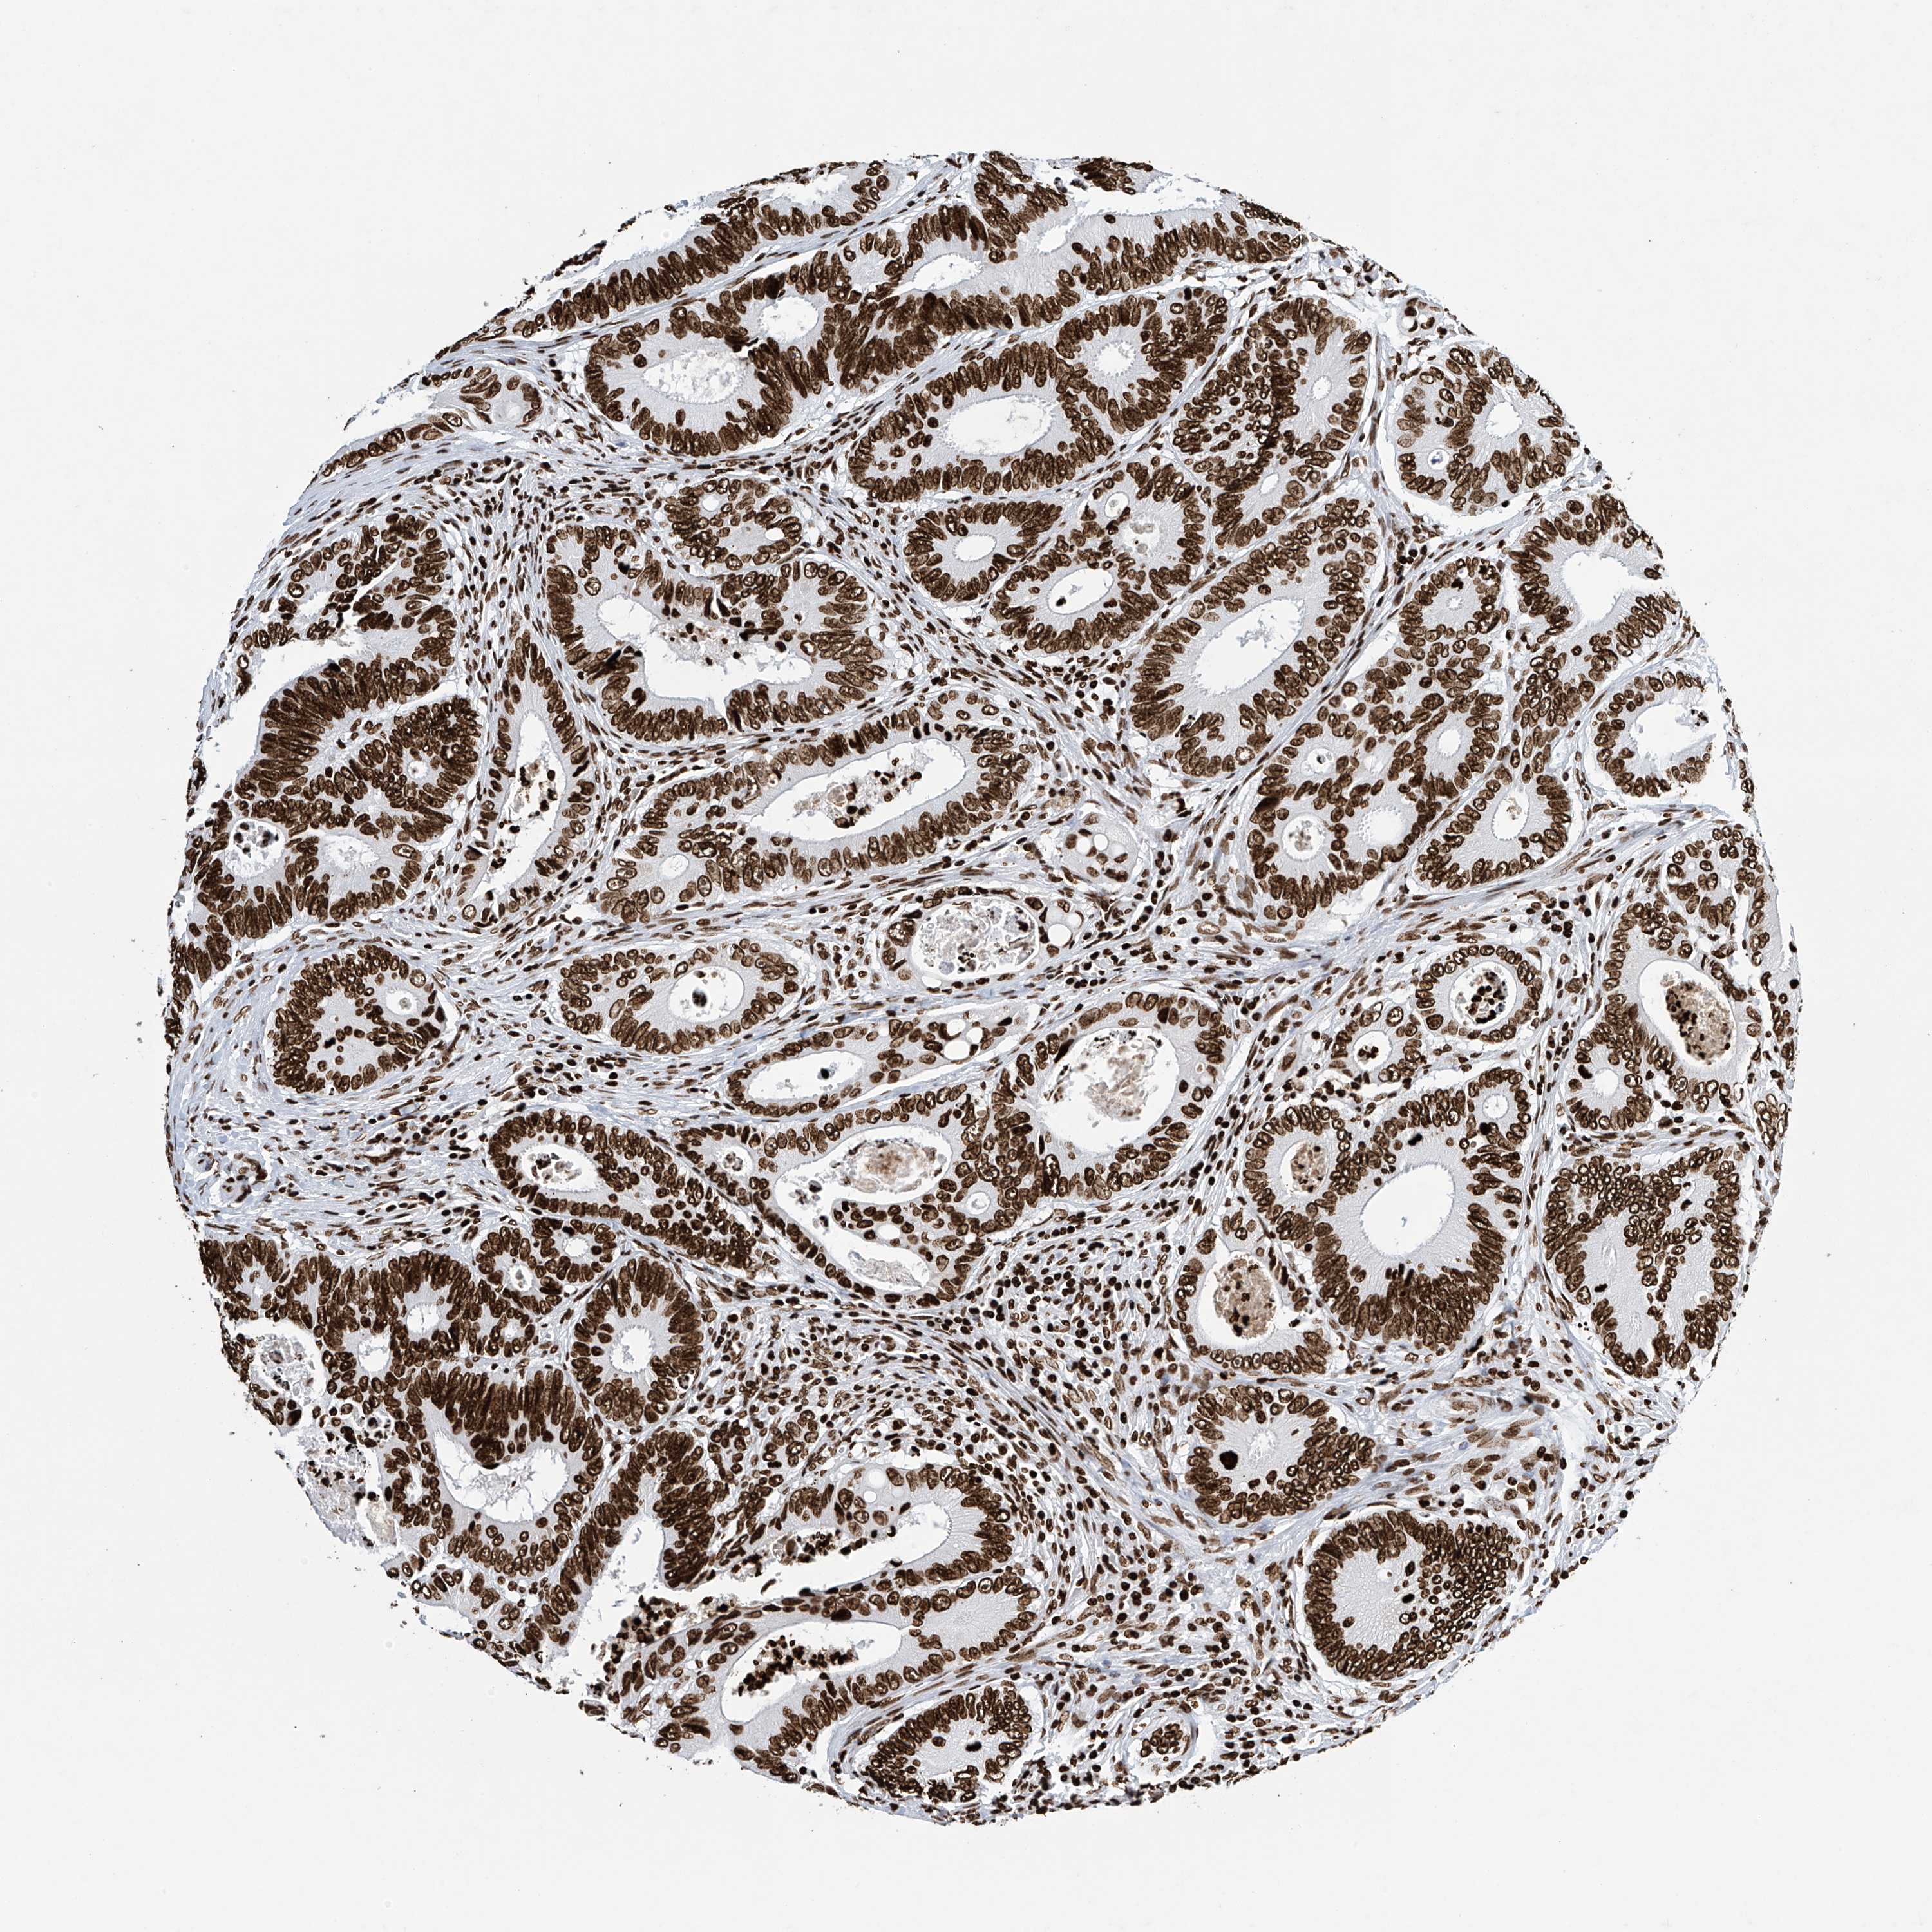

RECTUM ADENOCARCINOMA (TCGA) - Interactive survival scatter ploti

The Survival Scatter plot shows the clinical status (i.e. dead or alive) for all individuals in the patient cohort, based on the same data that underlies the corresponding Kaplan-Meier plots. Patients that are alive at last time for follow-up are shown in blue and patients who have died during the study are shown in red.

The x-axis shows the expression levels (FPKM) of the investigated gene in the tumor tissue at the time of diagnosis. The y-axis shows the follow-up time after diagnosis (years). Both axes are complimented with kernel density curves demonstrating the data density over the axes. The top density plot shows the expression levels (FPKM) distribution among dead (red) and alive patients (blue). The right density plot shows the data density of the survived years of dead patients with high and low expression levels respectively, stratified using the cutoff indicated by the vertical dashed line through the Survival Scatter plot. This cutoff is automatically defined based on the FPKM cutoff that minimizes the p-score. The cutoff can be changed by dragging the vertical line or by entering a cutoff value in the square labeled "Current cut-off".

Under the Survival Scatter plot the p-score landscape (black curve; left axis) is shown together with dead median separation (red curve; right axis). Dead median separation is the difference in median mRNA expression between patients who have died with high and low expression, respectively. It is calculated as follows: median FPKM expression of dead patients with high expression - median FPKM expression of dead patients with low expression. This is intended to aid the user in visually exploring custom cutoffs and the associated p-scores and dead median separation.

Individual patient data is displayed and can be filtered by clicking on one or more of the category buttons on the top of the page. Categories describing expression level and patient information include: high, low, alive, dead, female, male and tumor stages. The scale of the x-axis can be toggled between linear and log-scale by clicking on the "x log" button. Mouse-over function shows TCGA ID, patient information and mRNA expression (FPKM) for each patient.

& Survival analysisi

Kaplan-Meier plots summarize results from analysis of correlation between mRNA expression level and patient survival. Patients were divided based on level of expression into one of the two groups "low" (under cut off) or "high" (over cut off). X-axis shows time for survival (years) and y-axis shows the probability of survival, where 1.0 corresponds to 100 percent.

H4C16 is not prognostic in Rectum Adenocarcinoma (TCGA)

Best expression cut offi

Based on the FPKM value of each gene, patients were classified into two groups and association between prognosis (survival) and gene expression (FPKM) was examined. The best expression cut-off refers the FPKM value that yields maximal difference with regard to survival between the two groups at the lowest log-rank P-value. Best expression cut-off was selected based on survival analysis .

When clicking on this number, the vertical dashed line indicating cut-off, the interactive survival plot, and the Kaplan-Meier curve will be adjusted to show results based on the best expression cut-off.

: N/A

Median expressioni

Median expression refers to the median FPKM value calculated based on the gene expression (FPKM) data from all patients in this dataset. When clicking on this number, the vertical dashed line indicating cut-off, the interactive survival plot, and the Kaplan-Meier curve will be adjusted to show results based on the median expression.

P scorei

Log-rank P value for Kaplan-Meier plot showing results from analysis of correlation between mRNA expression level and patient survival.

N/A

5-year survival highi

5-year survival for patients with higher expression than the expression cutoff.

For melanoma and glioma, 3-year survival is shown.

5-year survival lowi

5-year survival for patients with lower expression than the expression cutoff.

TCGA RNA samplesi

RNA-seq data is reported as average FPKM (number Fragments Per Kilobase of exon per Million reads), generated by the The Cancer Genome Atlas (TCGA) .

Normal distribution across the dataset is visualized with box plots, shown as median and 25th and 75th percentiles. Points are displayed as outliers if they are above or below 1.5 times the interquartile range. FPKM values of the individual samples are presented next to the box plot.

Average pTPM 0.5

Number of samples 88